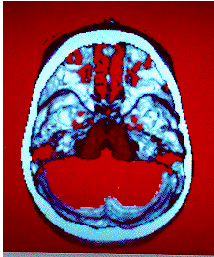

Thalami and base of the Skull.